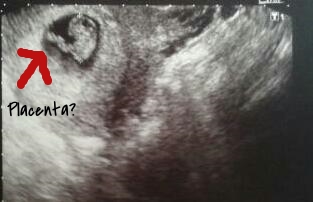

I know this is a crapshoot, but what would my baby be based in Ramzi's theory? This was transvaginal at 6w5d.

VERY slight girl lean, the white thick line is forming in the middle , bottom, but more to the left. Ramzi's Theory For Predicting Baby's Sex - Sex Prediction tests pt1 - Ilithyia's Love Full Spectrum Services

So to me the baby and placenta looks like it's on the right in the pic, but it's really on the left? Just want to make sure I'm seeing it right. :)